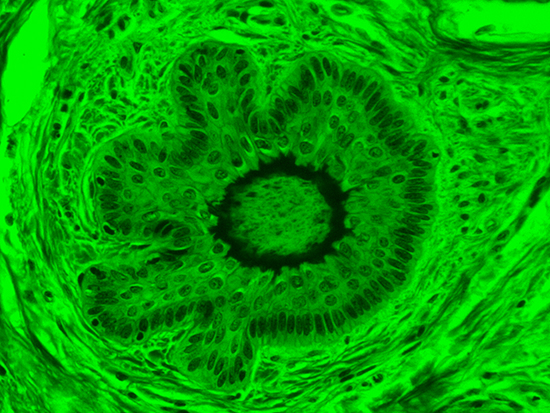

Masson's trichrome stain is incredibly effective in differentiating cells and their components from the surrounding connective tissues. One of the most common stain types, which has been used on the dermal tissue sample seen in the images within this article, yields a number of colors where cell nuclei appear dark red, collagen and other tissues appear green or blue, and cell cylasm appear red/purple (Jones, 2010). These stains have been imaged under brightfield and darkfield illumination, and then again with specific filters to selectively focus on the cellular constituents of the epidermis. The primary application for the epidermal trichrome stains is differentiating healthy collagen and muscles from connective tissues onset with tumorigenesis. Typically the tumors proliferate from muscle cells and fibroblasts deep in the dermal tissue (Blitterswijk, 2010).

Figure 3: Brightfield Image of Dermal Tissue filtered with Green

When comparing Figure 3 with Figure 4, there is once again a significant visual difference. The most obvious feature is the change in color from green to red due to a different hardcoated filter being positioned in the optical path. The less obvious difference is the varying contrast levels caused by the filters at specific regions of the dermal tissue. For example, Figure 3 exhibits a distinct ring at the central region of the cell with additional matter within. In Figure 4, the ring is extremely faint and the internal matter is not visible. With that said, the cell and surrounding dense materials are more evident in Figure 3, whereas the muscle fibers and collagen are more pronounced in Figure 4.